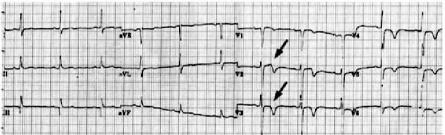

实验室检查显示心肌酶轻度升高,而其他常规实验室检查结果均在正常范围内。下图为患者的初始心电图。

图1:初始心电图患者的初始心电图显示窦性心律正常,从V1-V4心包导联开始双相T波,V3时ST段轻度抬高, 提示Wellens综合征A型。